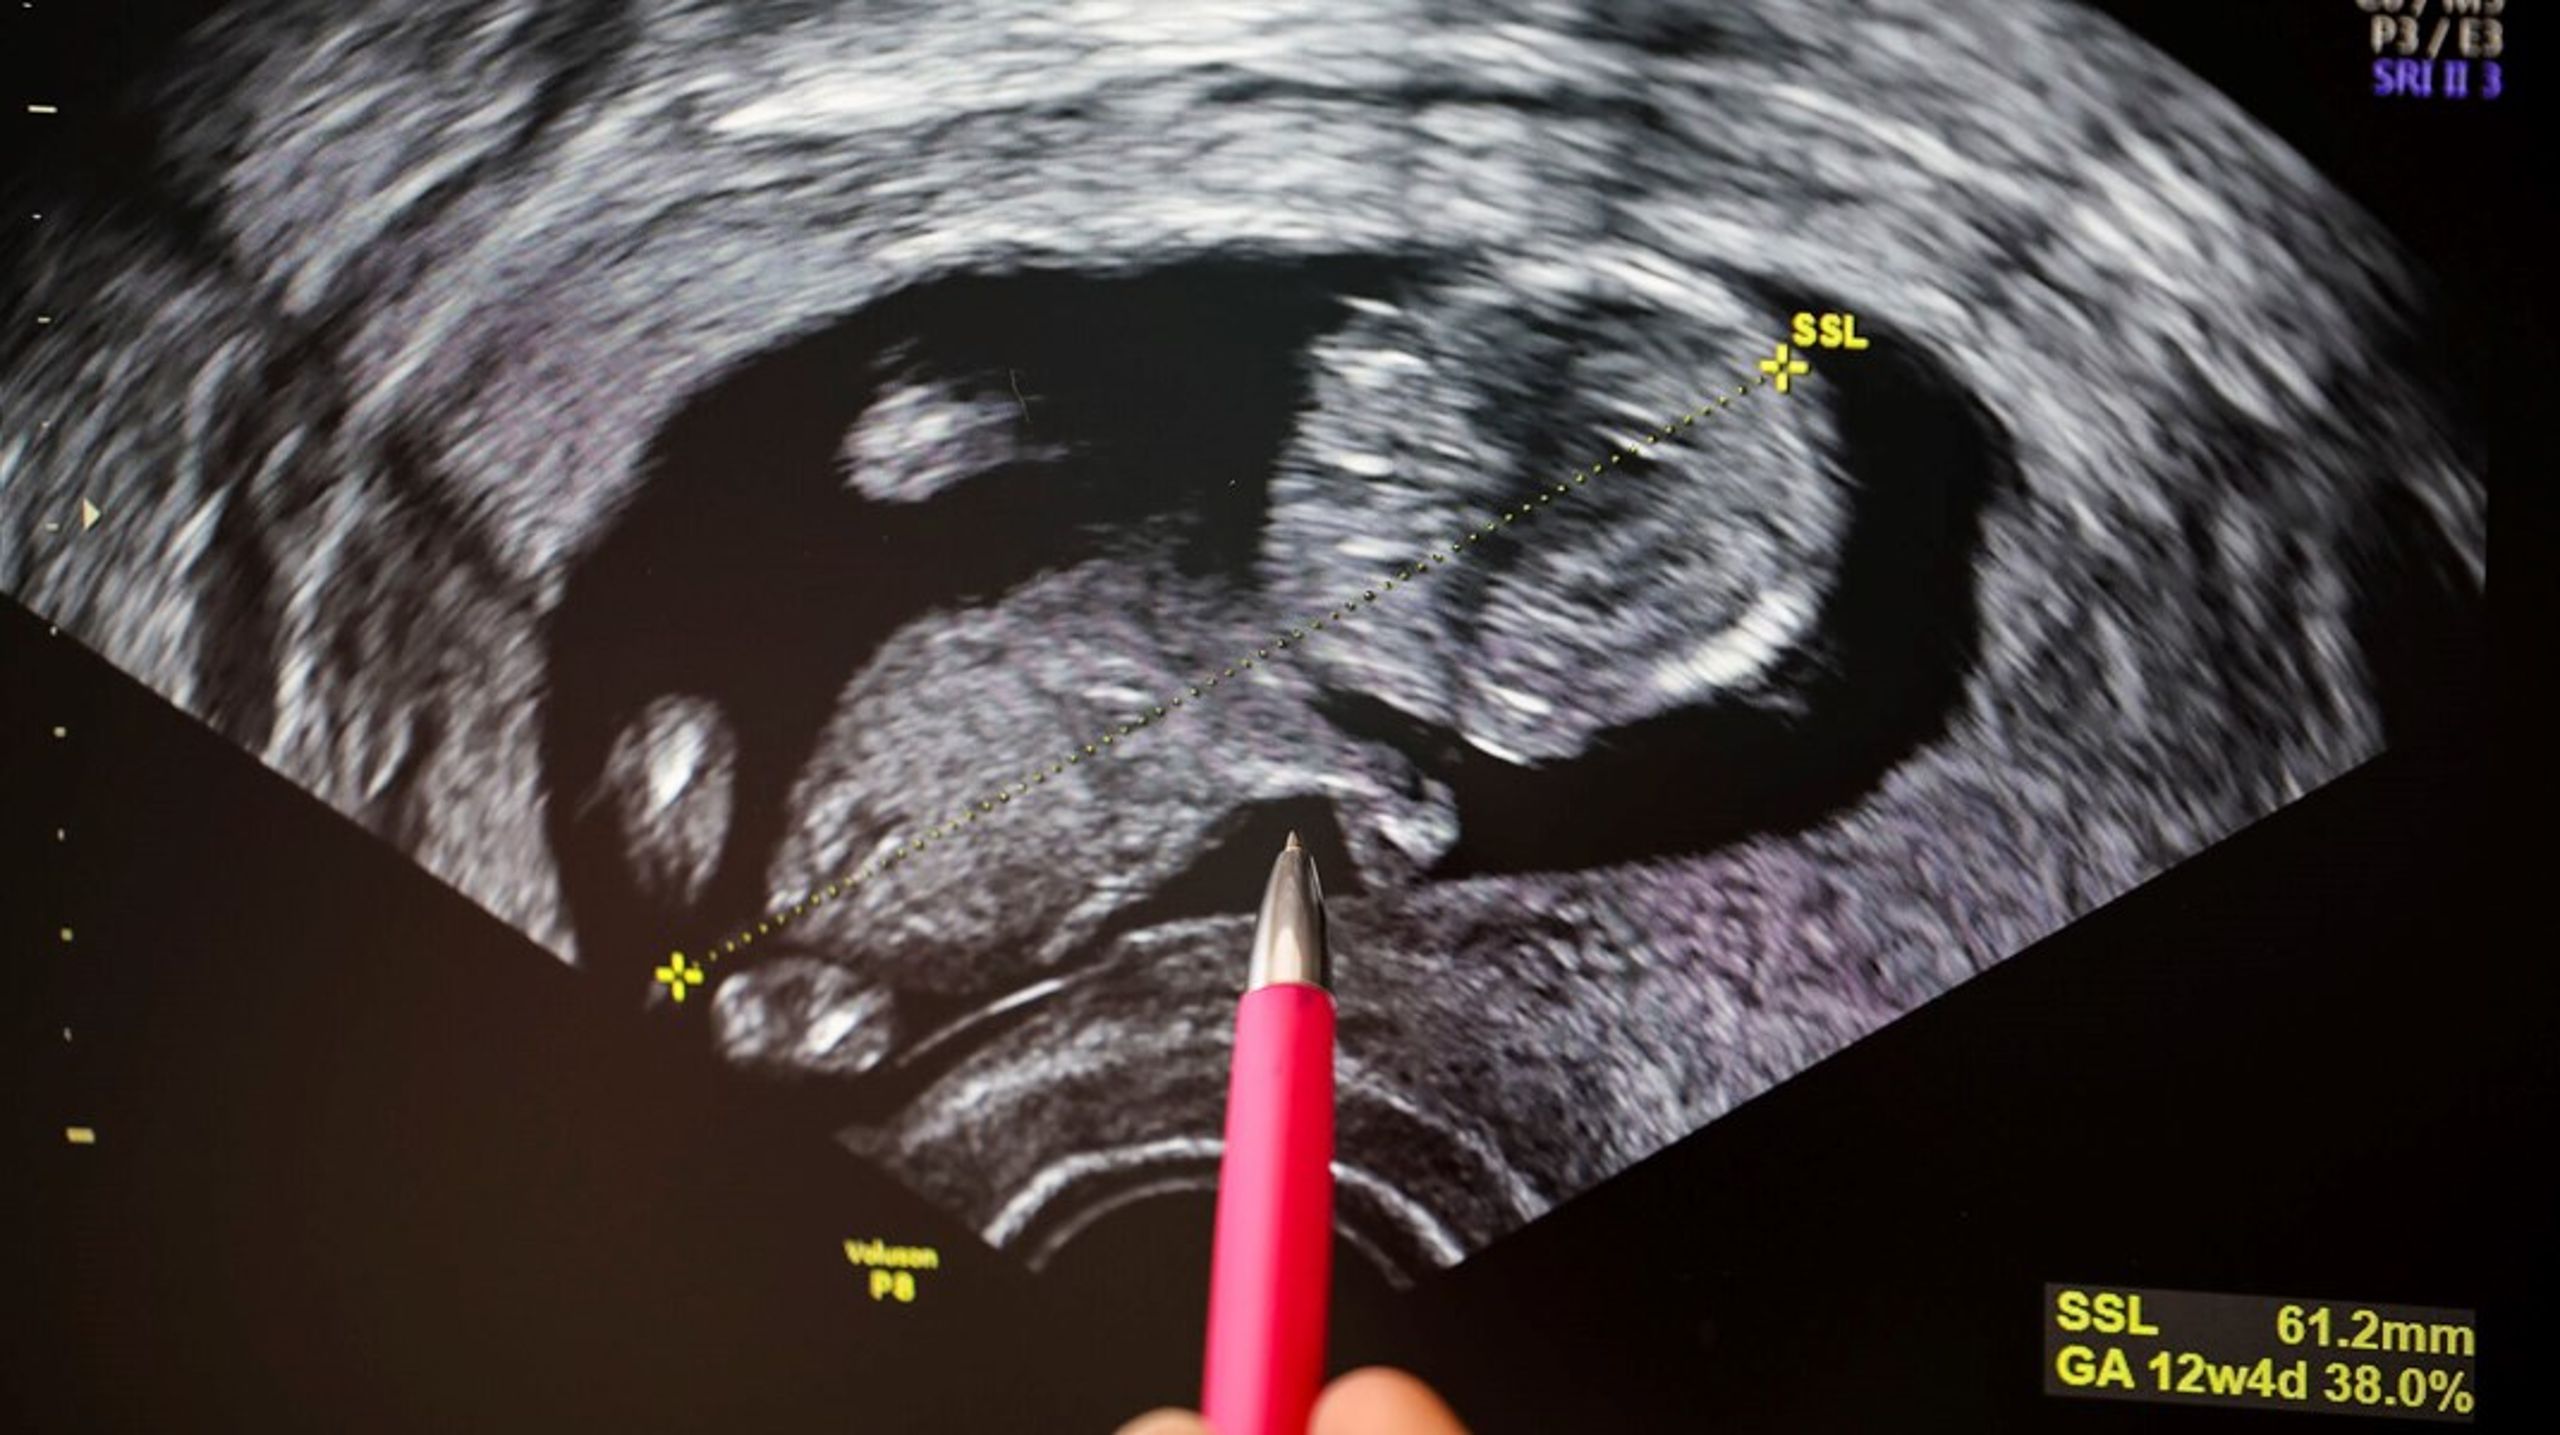

Er du gravid i et område med en høj koncentration af PFAS i drikkevandet, kan du se frem til at føde en baby, der vejer mindre end gennemsnittet.

Her påvises det, at gravide kvinder, der bor i områder med drikkevand over grænseværdien for PFAS-forbindelsen PFAS4, føder børn, der vejer 80 gram mindre end landsgennemsnittet.